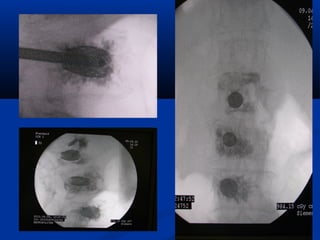

Spondylodesia

Percutaneous

Spondylodesia percutaneous

& Interbody spacer

Percutaneous spondylodesia

and interbody spacer